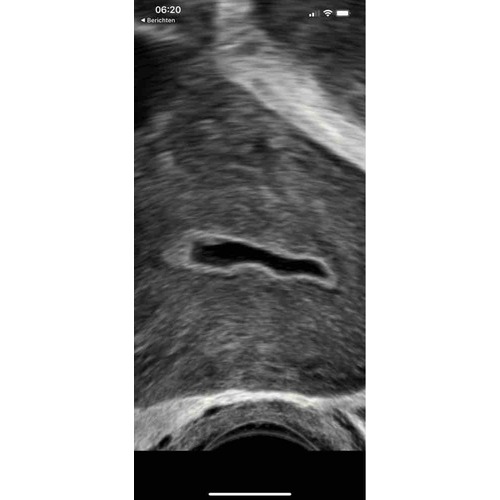

Ja snap ik maar tijdens de innesteling is de baarmoederslijmvlies 12.28 en nu is het bijna niks maar wel vruchtzakje ect te zien maar me baarmoederslijmvlies is te dun zij die gynaecoloog🥺🥺 en ik weet nu niet of t goed is